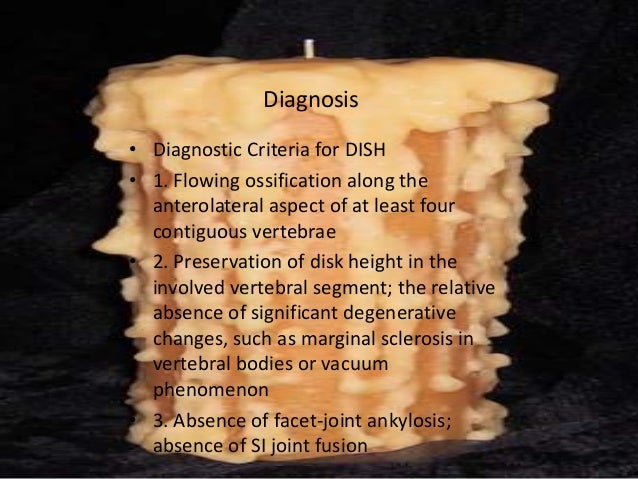

Even low energy trauma could lead to a serious fracture. So someone with the condition suffers a fall and lands on their back has an increased risk of a fracture. A healthy spine is flexible enough to distribute the force from a fall or hit and prevent injury. It is usually asymptomatic/without symptoms or mildly symptomatic. Diffuse Idiopathic Skeletal Hyperostosis Symptomsĭiffuse Idiopathic Skeletal Hyperostosis SymptomsĪn important reason that diffuse idiopathic skeletal hyperostosis is not recognized and underdiagnosed is that many individuals do not experience symptoms.